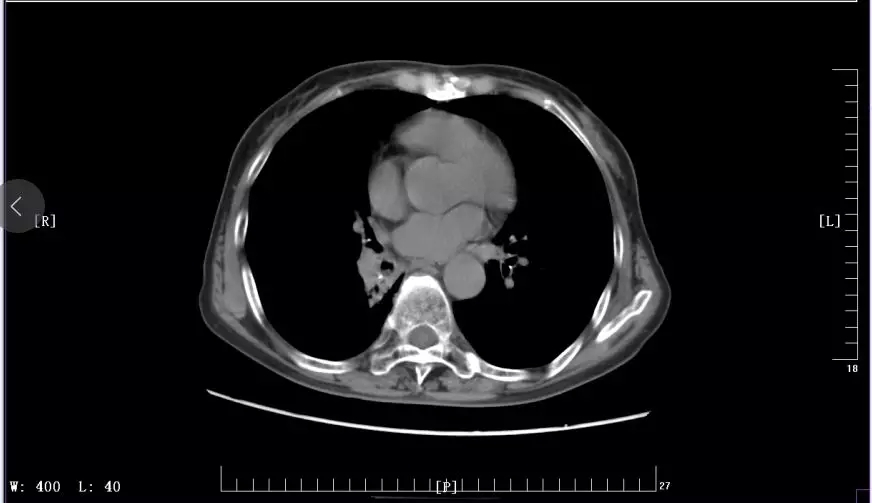

下图是徐丽参加KEYNOTE-407临床试验前后CT影像对比图:

2017年11月治疗前CT影像

2018年6月治疗中CT影像

2018年12月最近一次治疗后CT影像

张老回忆到:从老家到医院的这几个小时段路程中,他们走的漫长又艰辛,经过一系列的诊断,徐丽被确诊为右肺鳞癌IV期,肺鳞癌占原发性肺癌的40%-51%。晚期肺鳞癌由于尚未发现明确的驱动基因,没有较为有效的靶向治疗药物,目前仍以化疗治疗为主,但有效率较低,仅达到30%左右,晚期肺鳞癌患者的生存时间较短,仅能够维持一年左右。噩梦般的现实,使徐丽夫妇无力还击,但医生的耐心诊治,护士的关心照顾又让他们重拾信心,重新建立起抗击病魔的信念。但病魔仍在一步步入侵,肿瘤病灶增至8.5cmx6.8cm,癌细胞已转移到淋巴结,开始出现大量胸水,疾病产生的疼痛也愈加难忍。病魔越来越嚣张,治病造成的经济负担也让一个普通家庭越来越难以承受。漫漫长夜,张老辗转难眠,想着与老伴一路走来的不容易,对老伴既是感激又是内疚,但望着眼前虚弱不堪的老伴,张老不能倒下,他必须坚强,为了老伴,也为了这个家。